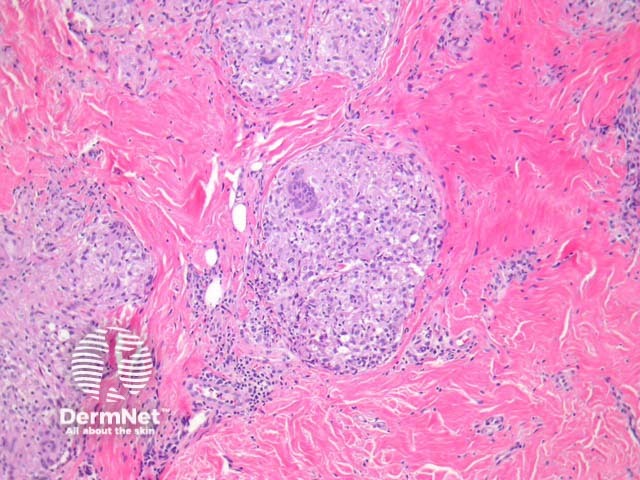

Lepromatous leprosy – Underneath a normal epidermis and grenz zone, there are sheets or clusters of macrophages (figure 1). The macrophages have an abundant pink to pale cytoplasm which corresponds to numerous intracellular (parasitized) organisms (figure 2). The associated infiltrate is usually sparse and mainly lymphocytic. In older lesions, the macrophages may have a bubbly cytoplasm (figure 2). As opposed to tuberculoid leprosy, there are not well-formed granulomas or infiltration of nerves.

Figure 1

Figure 2